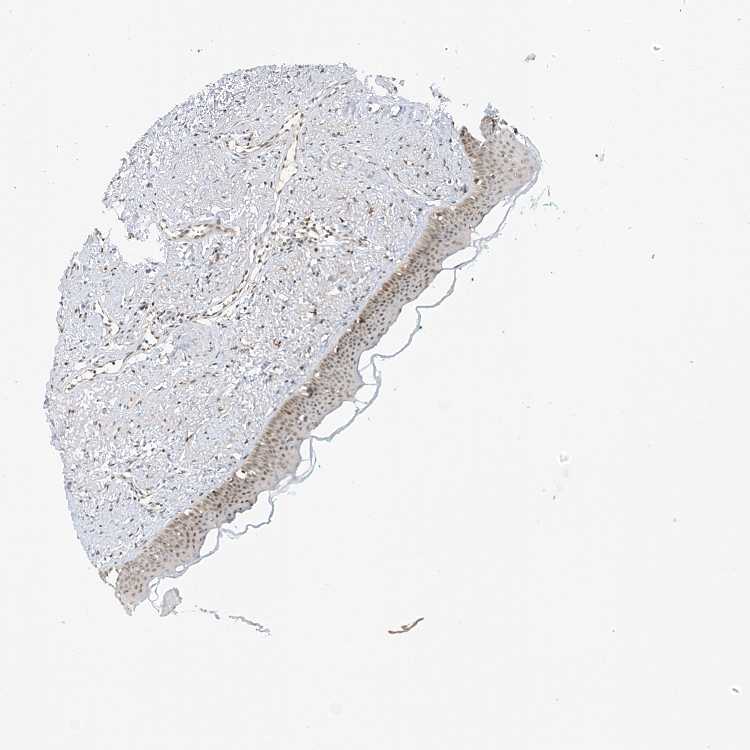

TISSUE PRIMARY DATA ORAL MUCOSA Show tissue menu

ORAL MUCOSA - Antibody stainingi

Antibody staining in the annotated cell types in the current human tissue is reported as not detected, low, medium, or high, based on conventional immunohistochemistry profiling in selected tissues. This score is based on the combination of the staining intensity and fraction of stained cells.

Each image is clickable and will lead to virtual microscopy that enables deeper exploration of all samples and also displays staining intensity scores, fraction scores and subcellular localization as well as patient and tissue information for each sample.

Antibody HPA023924Antibody HPA031526

Squamous epithelial cells MediumMedium